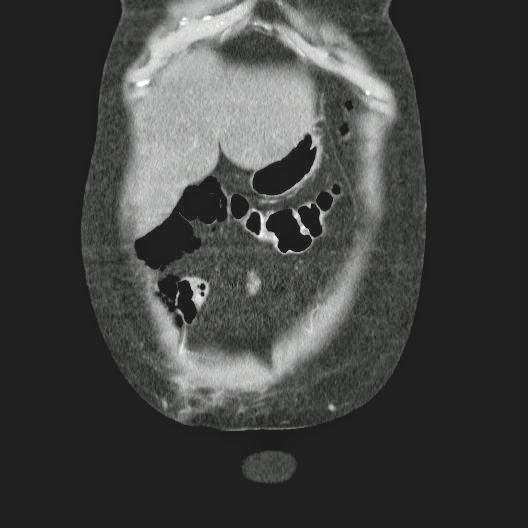

Paciente con antecedente de ALIF (Fusión lumbar intersomática anterior) 360 grados L5-S1 hace siete meses, quién presenta herida de abordaje anterior con dehiscencia de sutura, con cierre por segunda intención, quien consulta por cuadro clínico de dos días de secreción purulenta en herida quirúrgica, niega fiebre, niega otras sintomatología, refiere episodios previos similares.

Paciente en POP de ALIF L5-S1 quien presento dehiscencia de la herida abdominal con ISO superficial ya tratada, sin embargo persiste con dehiscencia y desde ayer con supuración asociado a fiebre subjetiva. Se realiza eco abdominal con colección en pared sugestiva de absceso, elevación de RFA por lo cual se considera se debe hospitalizar para manejo antibiótico, drenaje de la colección, manejo médico y vigilancia neurológica.

- ¿Hallazgos Escanografia?

2. Hay una colección de la pared abdominal en el flanco derecho, que realza en la periferia con el contraste, e intraabdominal tiene aire pero no me parece colección intraabdominal porque la grasa no está alterada.

3. Recomendado: Drs. JOSÉ M. ZUÑIGA A.1, FRANCO ORELLANA G.1, MARCELO CASTRO S.3, ROLANDO SEPÚLVEDA D.4, HORACIO RÍOS R.4, Int. VELIA SALDÍAS H.2. Neumatosis Intestinal: Caso Clínico-Radiológico. Pneumatosis intestinalis. A case report. Rev Chil Cir v.61 n.1 Santiago feb. 2009